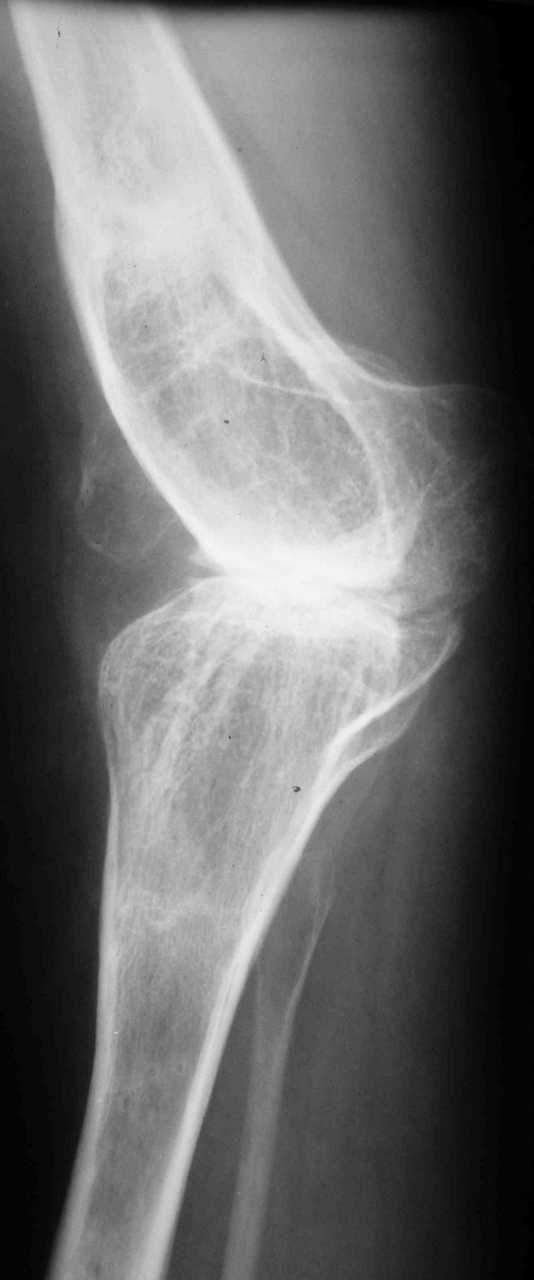

Уважаемые коллеги! К мне обратилась моя бывшая пациентка, 22 лет, с просьбой об эндопротезировнии коленного сустава. От артродеза категорически отказывается.DS: Врождённая аномалия развития левой нижней конечности. Состояние после удлинения бедра и голени (около 45 см). Варусная деформация шейки лев. бедра. Лев. коксартроз II ст. Лев. гонартроз III ст. Разгибательная контрактура лев. коленного сустава. Парез малоберцового нерва слева. Укорочение лев. н/конечности 1,5 см. Жалобы: на боли и нарушение функции в лев. коленном суставе.St. localis: ходит в брейсе с опорой на 1 трость. Относительная длина ног S – 1,5 см. Движения в лев. т/б суставе: сгиб. 70, разг. 180, привед. 60, отвед. 110, вн. рот. 20, нар. рот. 10; в лев. к/сус. пассивно: сгибание 0, разг. - 180+ 30; активно на переразгибание и из положения переразгибание на сгибание 2балла. Под нагрузкой вальгусно-рекурвационная деформация: клиничски на val. – 15-20, rec. - 30. Движения в лев. голеностопном суставе (акт./пас.): тыл. фл. 0/90, под. фл. 170, отвед. 10/15, прив. 25. Функция в других суставах не нарушена.Предполагаю, что наиболее лучшим вариантом будет двух этапное протезирование. На первом этапе – устранить антекурвацию на бедре аппаратом Илизарова; вторым этапом – протезирование – заднее-стабилизирующим протезом фирмы «Zimmer», т.к. маленькие размеры бедренной и большеберцовой костей.Возможны ли другие варианты лечения? Возможно ли одно этапное протезирование?Целесообразно ли в данном случае протезирование? Может быть не стоит идти «на поводу» у пациентки.Буду очень признателен всем, кто откликнется на мою просьбу.С уважением Игорь Атманский.

Трудно понять общую картину по "короткому" снимку в одной проекции. Желательно было бы увидеть нормальный снимок в двух проекциях, оптимально еще и снимок, захватывающий всю ось конечности от тазобедренного до голеностопного сустава.

Учитывая неоднозначность данного случая, такой снимок все равно надо делать.

Что касается самых общих соображений, то вызывает сомнения состоятельность боковых связок.

Учитывая сложность случая, здесь явно показан хинч. Однако ставить хинч молодой женщине.